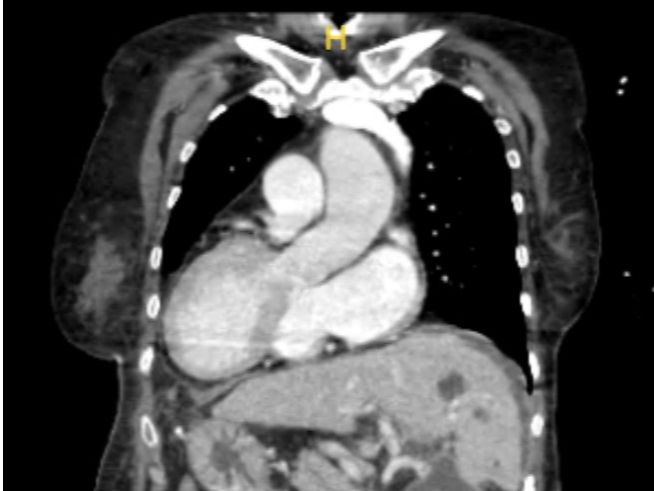

【人民日报】心脏在右、肝脏在左,逸仙团队为“镜面人”完成全内脏反位肝移植

赵女士(化名)是发生率仅为约两万分之一的全内脏反位人群,即俗称的“镜面人”。67岁的她体内的器官和常人完全相反,近日,bat365在线中国登录入口孙逸仙纪念医院副院长刘超教授带领医院肝移植团队为身患肝功能衰竭、肝癌等疾病的赵女士成功开展了全内脏反位肝移植术。手术顺利进行,团队用精湛的技巧克服全内脏反位的困难,助“镜面...